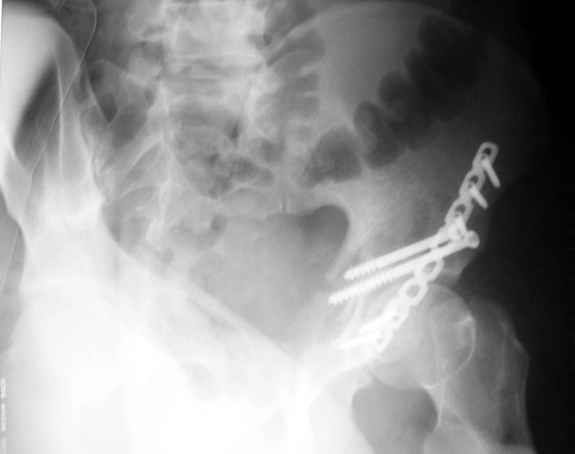

Уважаемые коллеги,Мужчина 36 лет от роду попал в ДТП 24.08.04 Рентгенограммы в приложении.

Не дождавшись советов, в понедельник прооперировал больного, заняло времени..., но все сделал в один этап: сначала фиксировал ипсилатеральный перелом бедра и шейки реконструктивным гвоздем Smith&Nephews, потом из расширенного илеофеморального доступа фиксировал перелом крыла подвздошной кости тягловым винтом, нейтрализующей пластиной заднюю колонну, и тягловыми винтами 3,5 мм переднюю колонну.

Диагноз- перелом с вовлечением таза, разрыв правого сакро-илиак сочленения vertical shear injury, перелом крыла подвздошной кости?, перелом ацетабулум Т type или Both column?, перелом шейки бедра, перелом проксимального отдела бедра.

перелом крыла правой подвздошной кости, перелом обеих колонн вертлужной впадины, двусторонний перелом лонных костей (С2.2) повреждение передних связок правого крестцово-подвздошного сочленения,

ипсилатеральный перелом шейки и диафиза бедра.

К сожалению, набора для ретроградного или антеградного реконструктивного штифтования в операционной нет, поэтому доставка заняла н-ное время. Вопрос, который возник у меня- по поводу оптимальной тактики хирургии: вся фиксация в один этап из расширенного доступа или последовательно сначала бедро и позже реконструкция впадины, комбинированный доступ к впадине отдельно к передней и задней колоннам или из расширенного илеофеморального одного доступа. Все-таки решил остановиться на одноэтапном подходе и спустя 5 дней (как раз и наборы привезли) из расширенного илеофеморального доступа сначала фиксировал реконструктивным штифтом Smith&Nephews бедро и

шейку (благо перелом шейки 2 типа -относительно стабильный) затем фрагмент крыла подвздошной кости Lag screw, далее пластина на заднюю колонну и винты в переднюю колонну.(с размерами и направлением винтов ошибка вышла:-((, но интраоперационно у меня была полная уверенность , что винты *ушли* в лонную кость).